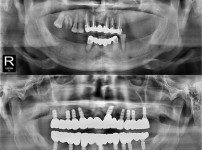

全口种植牙